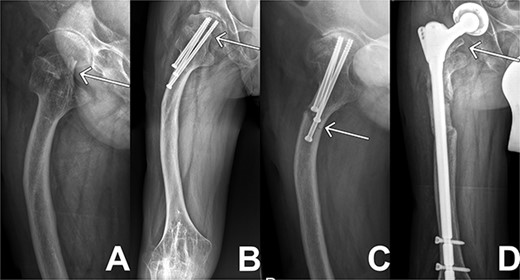

X-ray sequences of the right hip in different resolutions. (A) Representation of the medial femoral neck fracture before the first intervention as highlighted by arrow. (B) Osteosynthesis intervention of hip is highlighted by arrow few months after intervention. In addition, femoral deformity and knee rigidity are recognizable. (C) Periosteosynthetic fracture of the femoral shaft shortly before intervention. (D) Follow-up image of the inserted prosthesis material shows regular position.

In the following days the patient’s pain and infection parameters increased. With the suspicion of infection, open joint lavage, debridement with drain and Vancomycin insertion was performed 2 weeks later. The intraoperative specimen didn’t reveal any microbiological findings. The clinical situation and infectious parameters developed worse. The CRP values progressively increased reaching its peak shortly after revision at 454 mg/l, the PCT values reached levels of 1.94 μg/l when measured over several days. After revision, appropriate antibiotic therapy and proper prosthesis inlay in radiological controls, an exacerbation of the JIA was now suspected because of hints like diffuse myalgia and arthralgia with further increasing CRP and PCT parameters. A prednisolone shock therapy was initiated. Under this therapy, pain and infection parameters decreased, thus confirming the assumption. The patient could be discharged to outpatient follow-up treatment. The following controls confirmed a good clinical course as seen in Fig. 1(D).